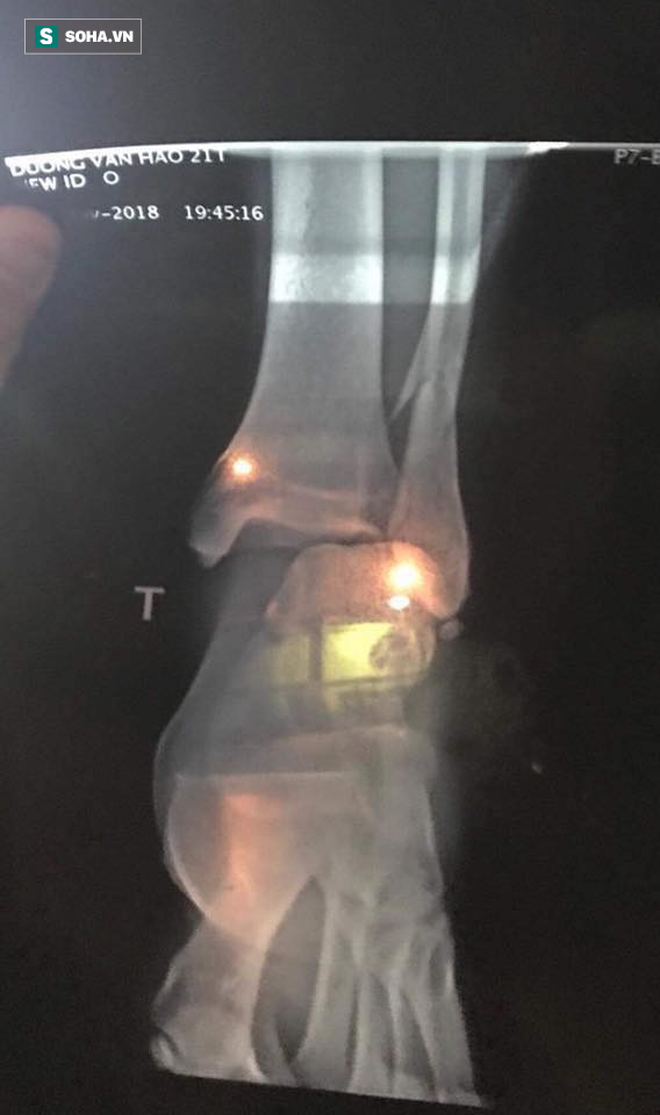

Cập nhật: Theo thông tin mới nhất, Dương Văn Hào bị gãy xương chầy, hiện đang phẫu thuật tại bệnh viện 108. Nhận định về pha vào bóng thô bạo của Tấn Tài nhưng chỉ phải nhận thẻ vàng, HLV Hoàng Anh Tuấn cảm thán:

Ảnh chụp X quang phần xương bị gãy, phải tiến hành phẫu thuật của Dương Văn Hào.